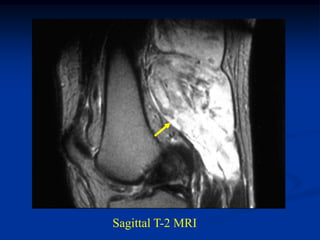

CLASSIC     Case #285         Sagittal T-1 MRI

67 year female with myxoid liposarcoma knee

Sagittal T-2 MRI

Axial T-2 MRI